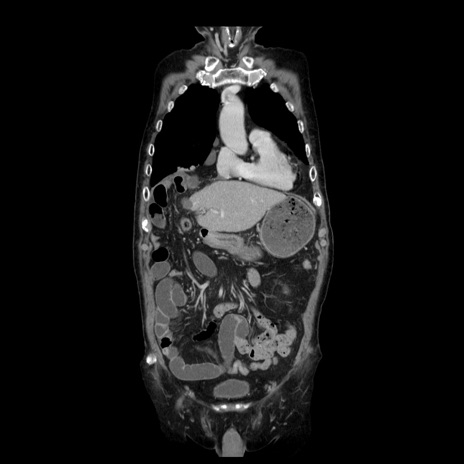

症例21(冠状断像)

【症例】70歳代男性

【主訴】腹痛

【現病歴】肝硬変・肝細胞癌にてかかりつけの方。約9時間前に食後より腹痛出現。症状が徐々に増悪し、嘔吐出現したため来院。

【既往歴】肝硬変、肝細胞癌(RFA、TACE後)

【身体所見】意識清明、表情苦悶様、BT 36℃、BP 129/78mmHg、P 88bpm、SpO2 97%(RA)、右上腹部から心窩部にかけて圧痛あり、反跳痛なし、筋性防御あり。

【データ】WBC 5800、CRP 0.16